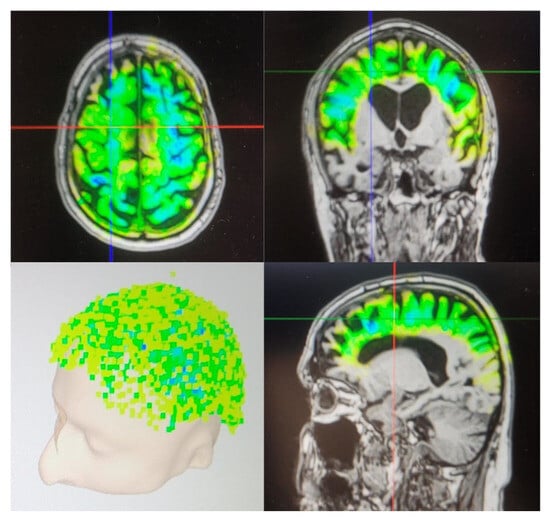

Neuroimaging Outcomes

- Beisteiner, R.; Matt, E.; Fan, C.; Baldysiak, H.; Schönfeld, M.; Philippi Novak, T.; Amini, A.; Aslan, T.; Reinecke, R.; Lehrner, J.; et al. Transcranial pulse stimulation with ultrasound in Alzheimer’s disease—A new navigated focal brain therapy. Adv. Sci. 2020, 7, 1902583. [Google Scholar] [CrossRef]

- Matt, E.; Kaindl, L.; Tenk, S.; Egger, A.; Kolarova, T.; Karahasanović, N.; Amini, A.; Arslan, A.; Sariçiçek, K.; Weber, A.; et al. First evidence of long-term effects of transcranial pulse stimulation (TPS) on the human brain. J. Transl. Med. 2022, 20, 26. [Google Scholar] [CrossRef]

- Dörl, G.; Matt, E.; Beisteiner, R. Functional specificity of TPS brain stimulation effects in patients with Alzheimer’s disease: A follow-up fMRI analysis. Neurol. Ther. 2022, 11, 1391–1398. [Google Scholar] [CrossRef]